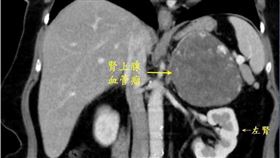

女上腹悶脹 竟是超罕見腎上腺血管瘤

60歲的蔡女士有輕微的高血壓和糖尿病,服藥多年控制穩...